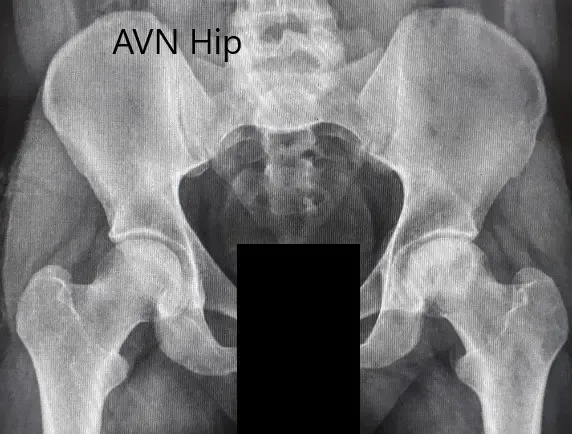

Imaging studies obtained in the form of an X-Ray suggested sclerosis of the left head of the femur. There were marked acetabulum changes. An MRI was further obtained suggesting avascular necrosis of the superior lateral head of the femur with changes in the acetabulum. There was marked hypointense areas on both T1WI and T2WIs.

Preoperative X-ray of the pelvis with both hips in anteroposterior view showing AVN of the Left Hip.